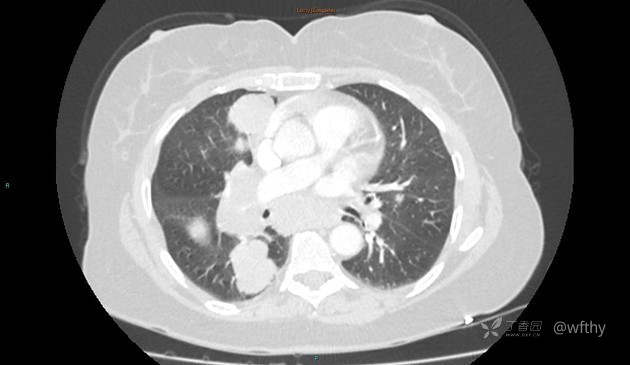

病例女65,头部肿块